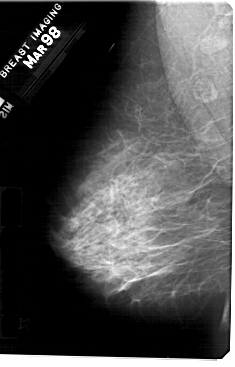

A_1363_1.LEFT_MLO

LEFT_MLO LINES 5491 PIXELS_PER_LINE 3511 BITS_PER_PIXEL 12 RESOLUTION 43.5 NON_OVERLAY